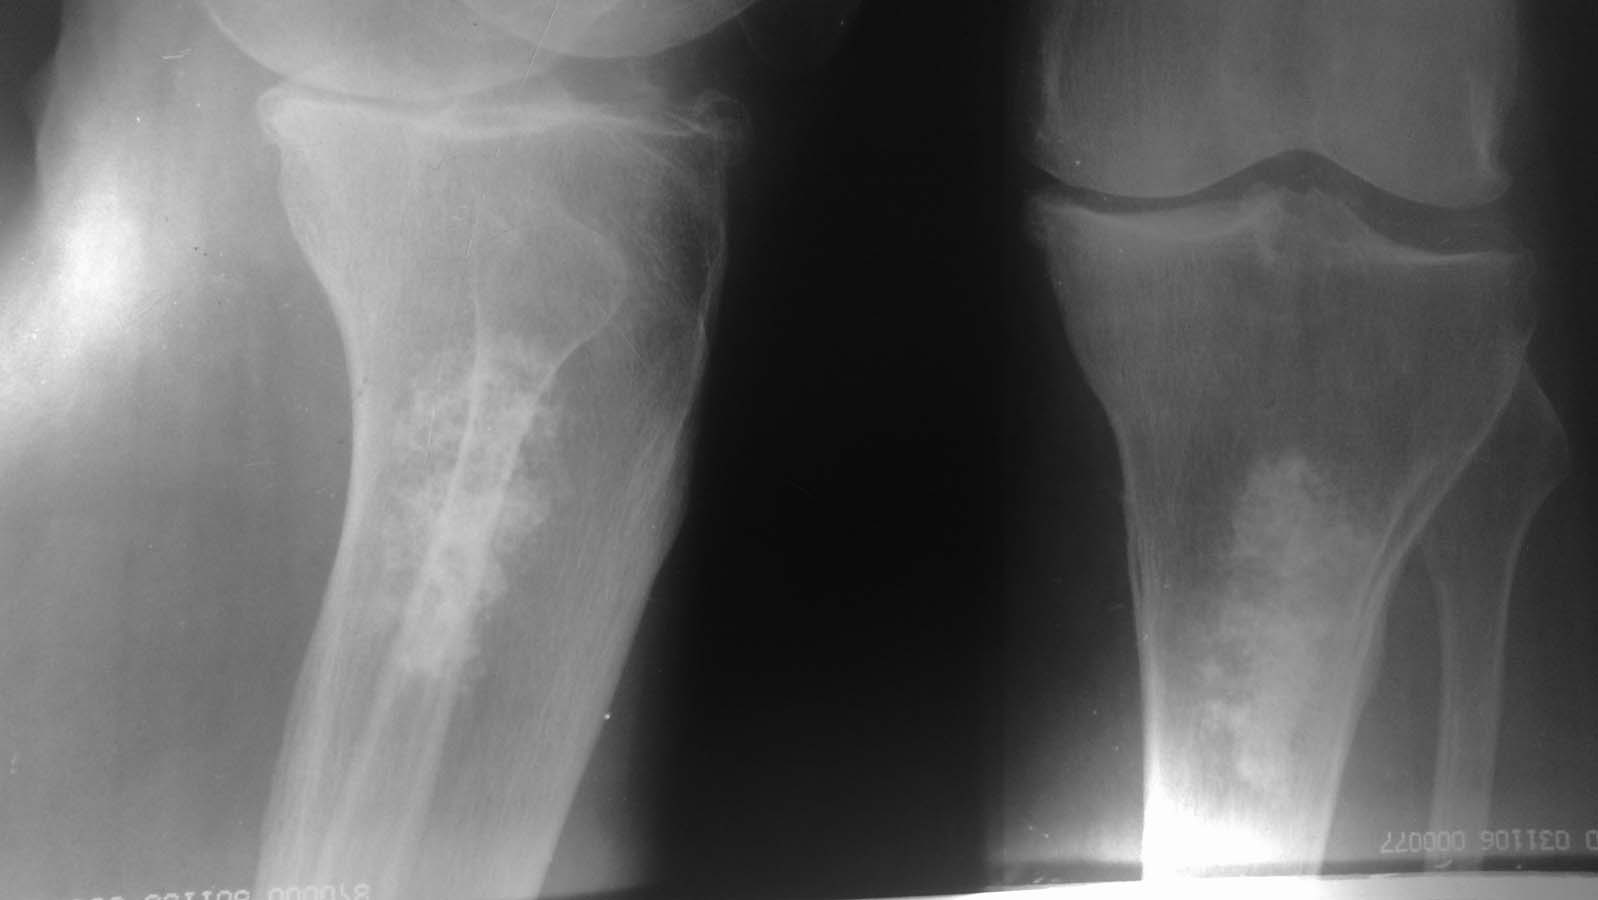

Пациентка 65 лет

что это может быть за образование?